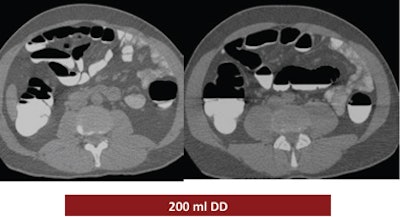

The study looked at three groups of 30 patients who underwent virtual colonoscopy after a same-day bowel preparation. Group 1 ingested 200 mL of undiluted DD the day of the exam, group 2 drank 100 mL of the agent the day of the exam, and group 3 ingested a low-dose polyethylene glycol (PEG) formula (macrogol) the two days before the exam, followed by 100 mL of DD the day of the exam.

According to the results, the mean segment quality values were 2.8 in patient group 1, 2.6 in group 2, and 3.2 in group 3.

"We had the best results in group 1, group 3 had the medium result, and group 2 had the worst results," he said. "The main difference was in the cecum," which produced a mean quality score of 2.3 for group 1, 1.6 for group 2, and 3 for group 3.

| Judged subjectively, the best overall prep quality was found in group 1, followed by group 3, with the worst results in group 2. By segment, the largest differences in quality were found in the cecum, with mean quality scores of 2.3 for group 1, 1.6 for group 2, and 3 for group 3. All images courtesy of Dr. Riccardo Ferrari. |

Group 1 had the best-quality results, with well-marked colonic mucosa but significant residual fluid. The use of 100 mL DD combined with low-dose polyethylene glycol over two days may have improved fecal tagging by softening the stool before the ingestion of the iodinated agent. In addition, no side effects were reported among the patients who ingested the PEG preparation for two days before the exam (group 3), Ferrari said.

| Above, the use of 200 mL DD in group 1 yielded the highest quality scores. While the colonic mucosa was well marked, significant volumes of fluid remained in the colon, similar to the 100 mL DD preparation (group 2, below). The use of 100 mL combined with low-dose polyethylene glycol over two days (bottom image) may have improved fecal tagging by softening the stool before the ingestion of DD. |